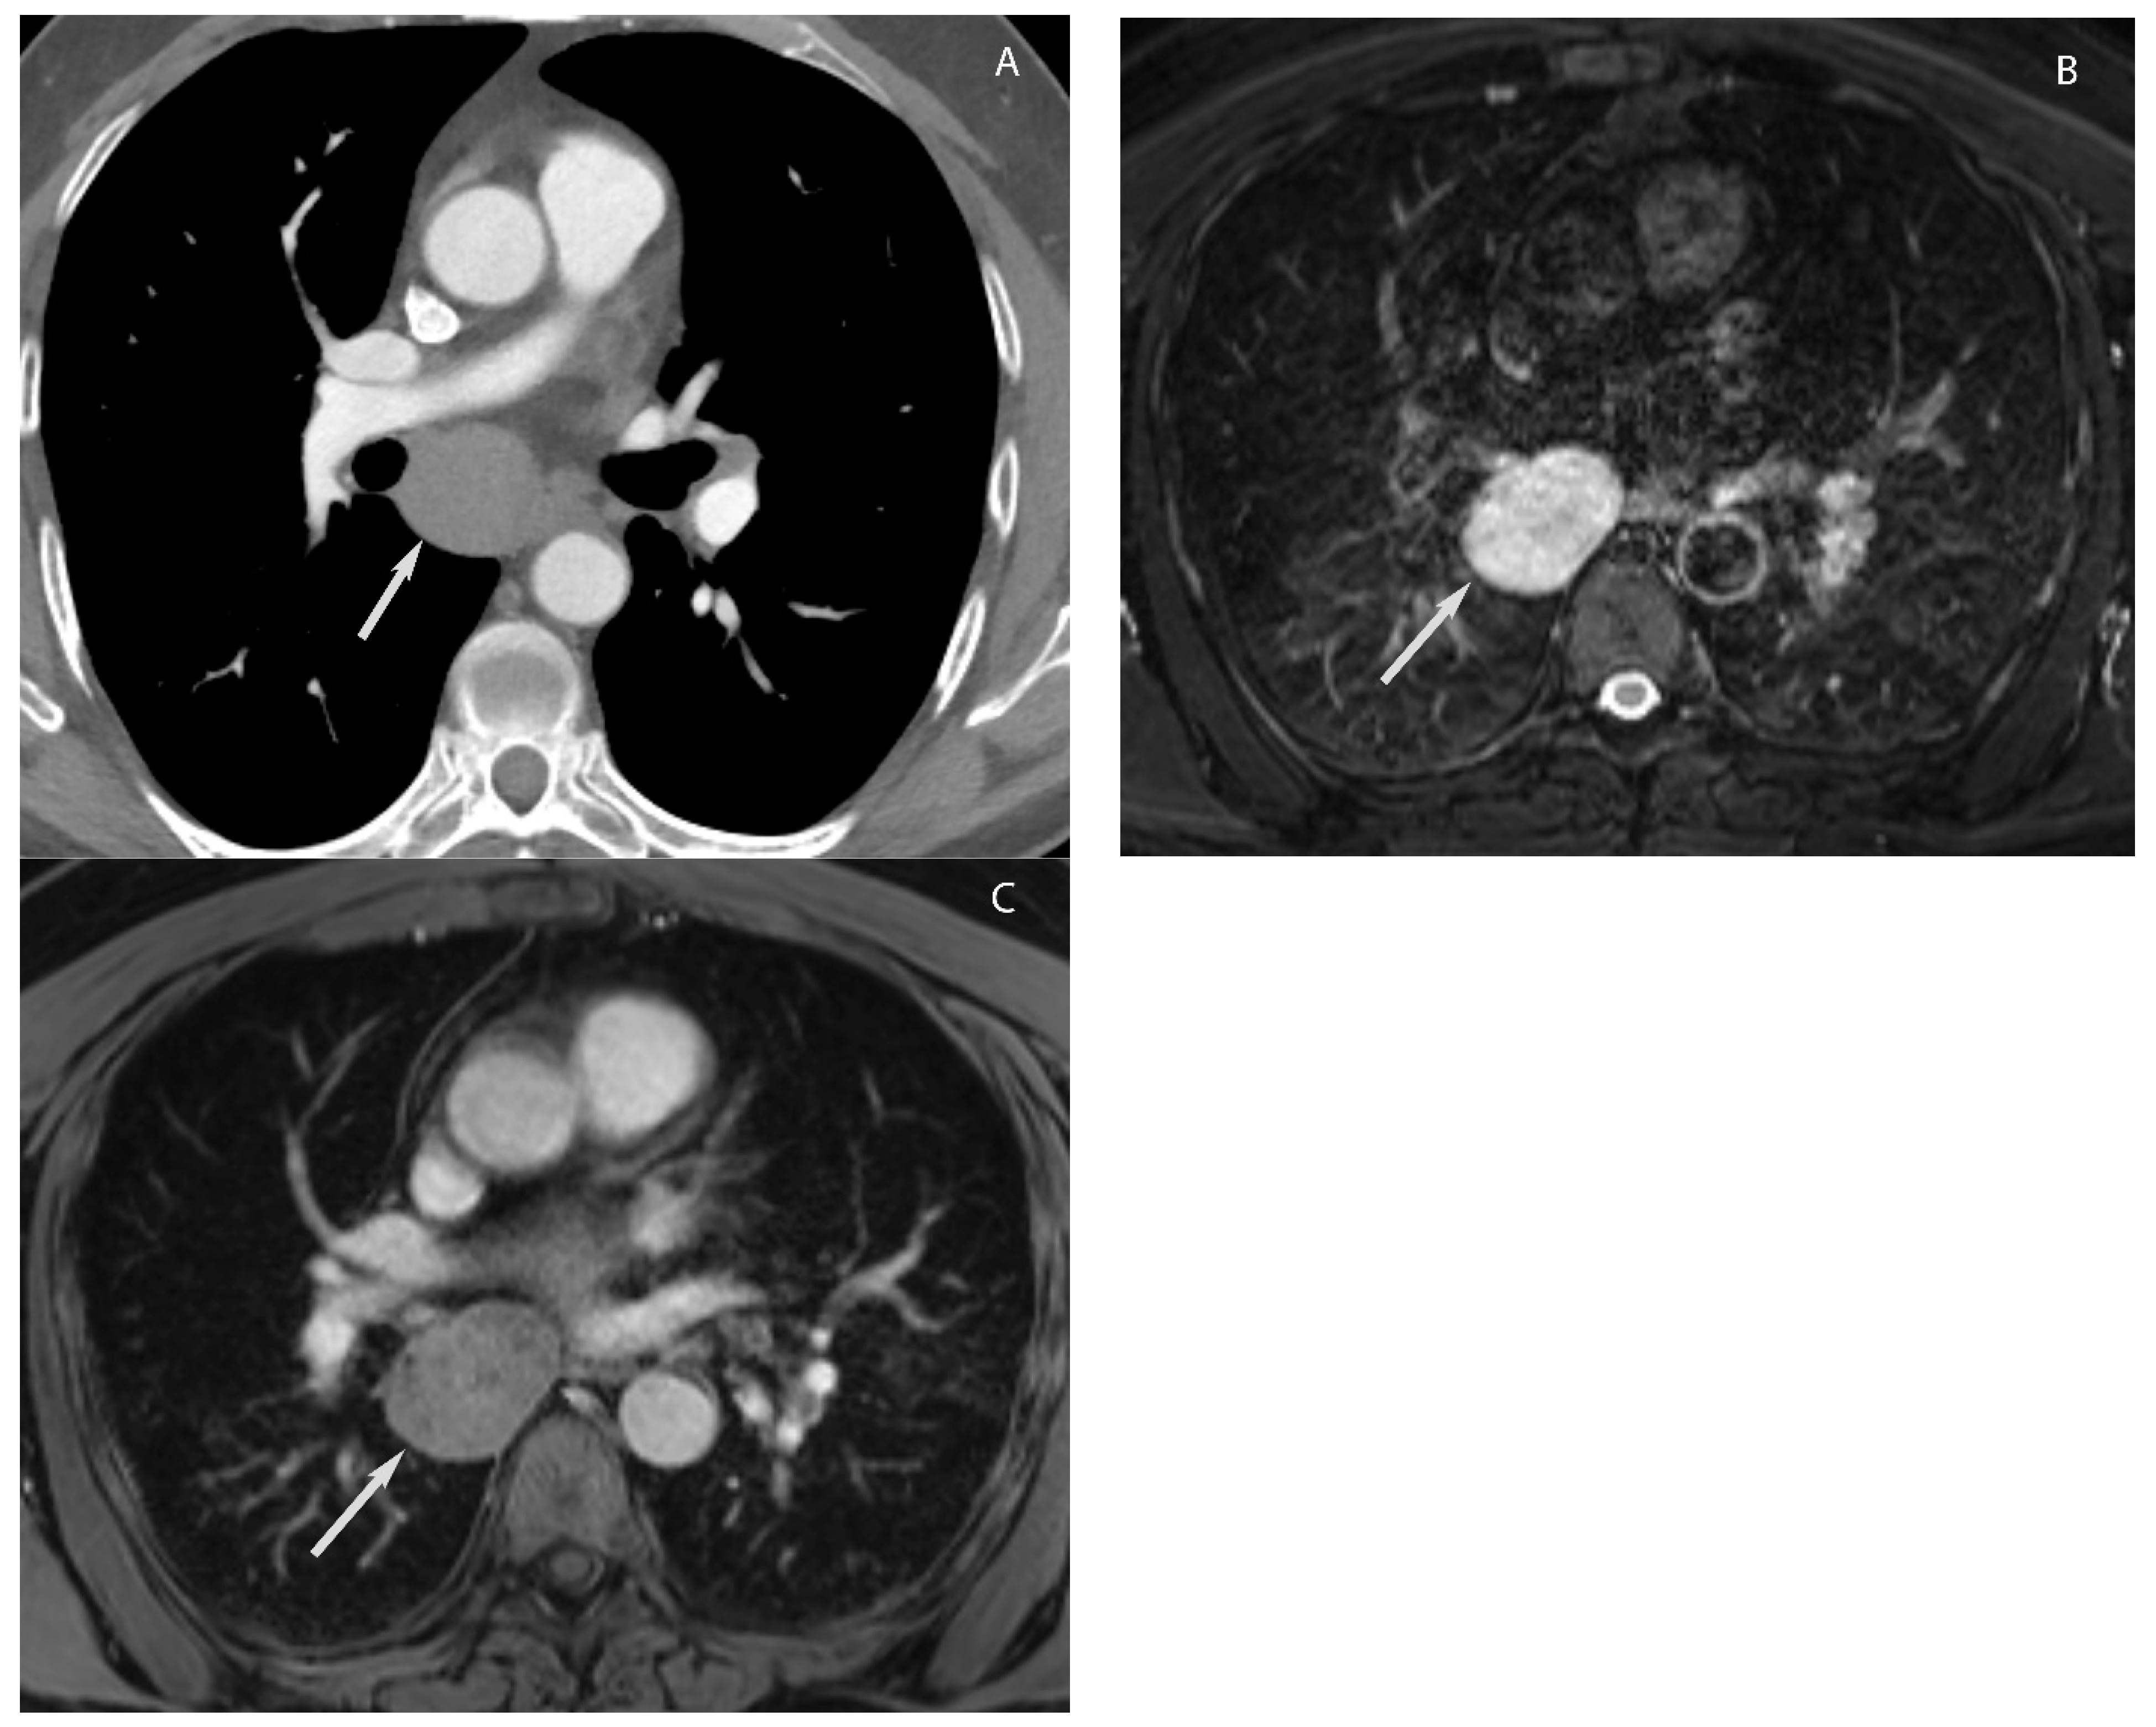

7. Germ Cell Tumors

9. Hypervascular Lesions